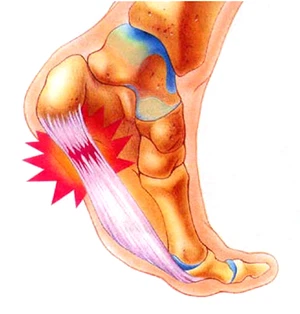

족저근막염은 쉽게 말해 발바닥 근육을 덮고 있는 막에 생긴 염증을 의미합니다. 족저근막은 발뒤꿈치뼈부터 발끝까지 이어지는 두껍고 강한 섬유로 발의 아치를 지탱해 발밑에 전달해지는 충격을 흡수하고 보행 시 발의 기둥이 되는 부분입니다.

이런 족저근막에 반복적인 미세 손상이 발생하게 되면 근막을 조직하는 콜라겐의 변성이 발생하며 이로 말미암아 염증과 진통을 보이는 질환을 족저근막염이라고 합니다.